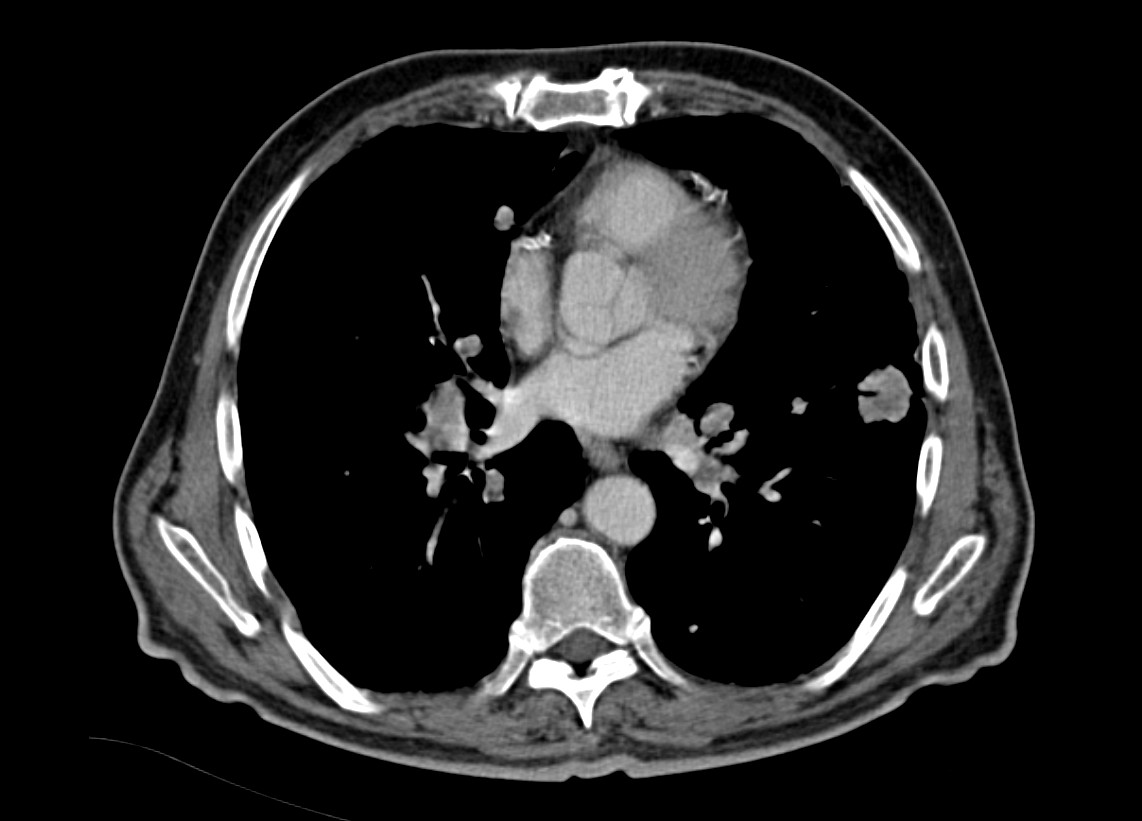

Αμφοτερόπλευροι πνευμονικοί όζοι ενδεικτικοί μεταστάσεων μελανώματος (Ευγενική παραχώρηση Dr. V. Penopoulos)